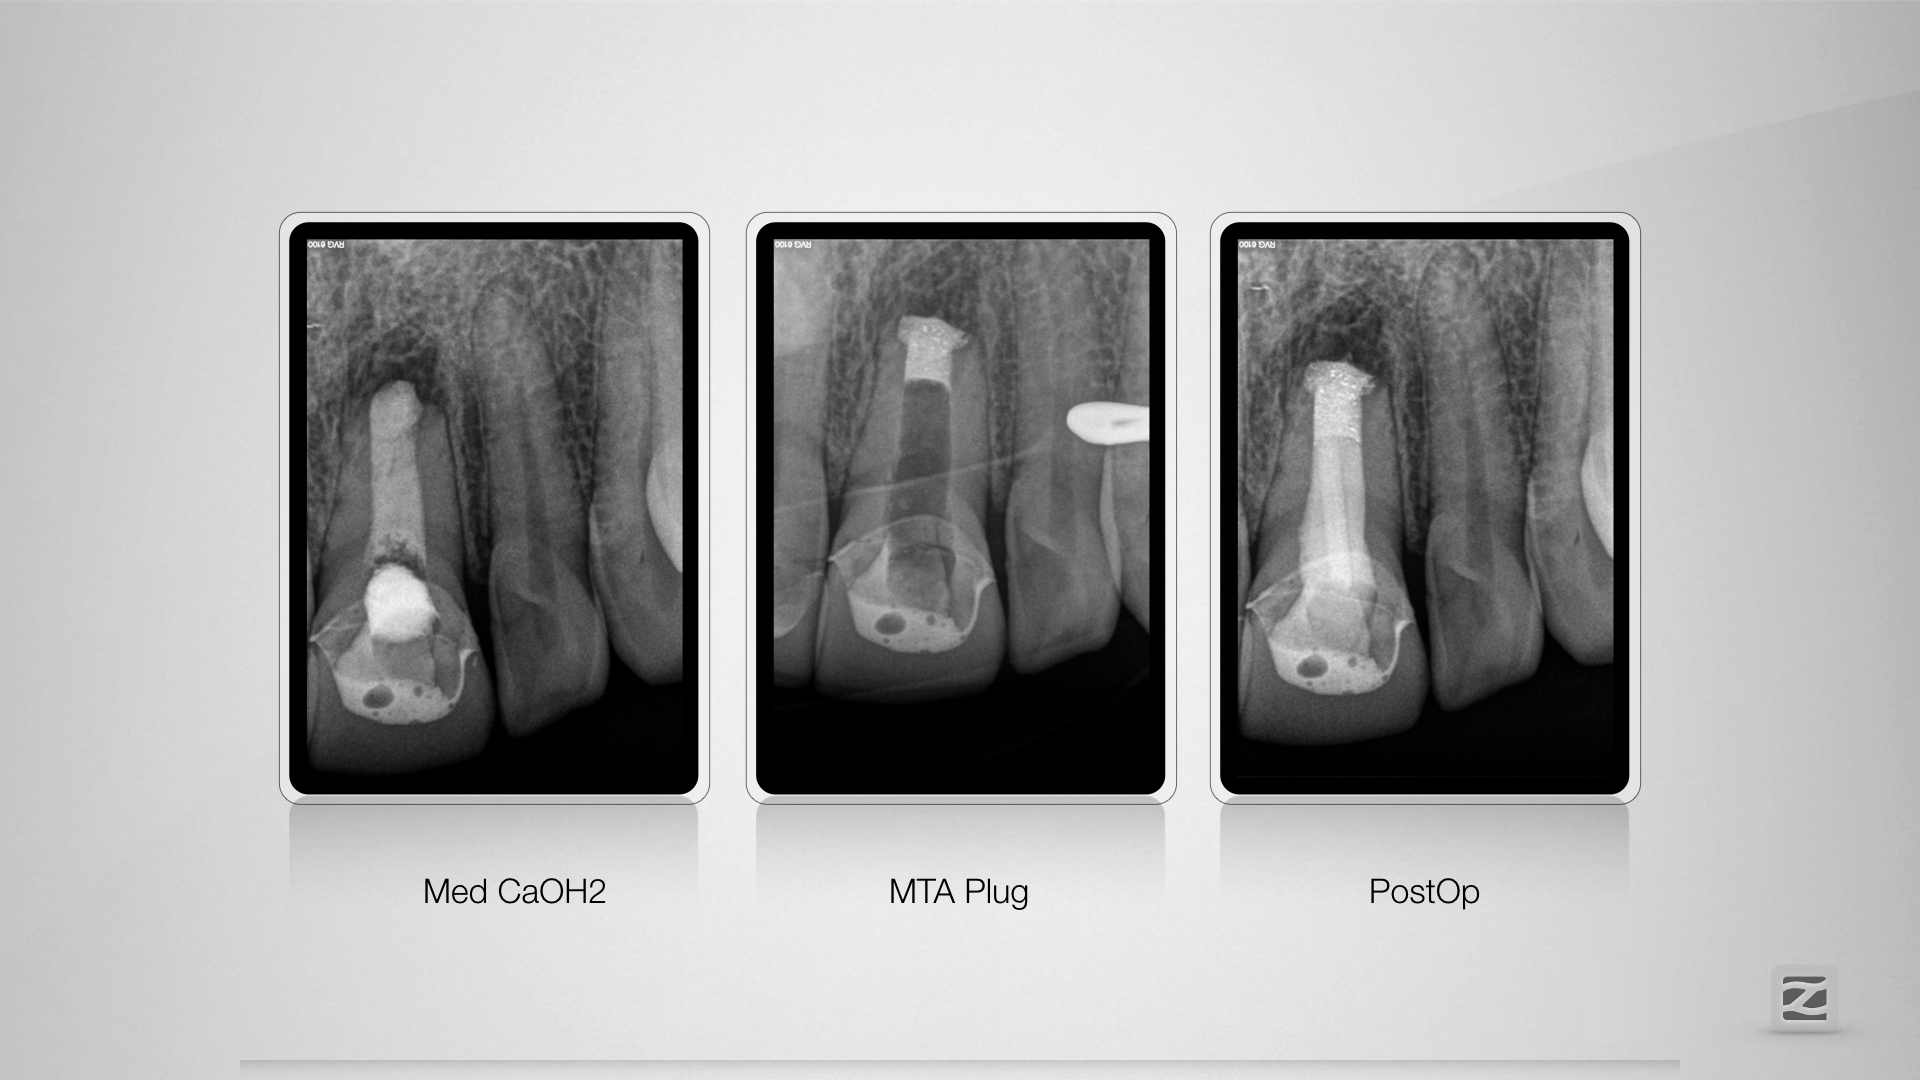

Der Schein trog!